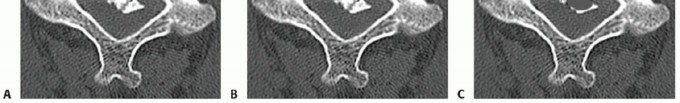

### TECH FIG 1 • Limits of corpectomy. A. The width of the corpectomy is based on that necessary to decompress the spinal cord and can be estimated on preoperative imaging. B. In general, a corpectomy spanning from the medial border of one uncinate to the other will be sufficient at the vertebral body level. (continued) The width of the corpectomy required to decompress the cord should be based on preoperative imaging studies (TECH FIG 1). Generally, sufficient decompression will occur if the width of the decompression spans from uncinate to uncinate. Wider decompressions beyond the medial border to the uncinates are typically performed at the disc level, where a combination of cord and root compression may occur, but are not necessary at the vertebral body level, where only the spinal cord is compressed.

TECH FIG 1 • (continued) C. At the level of the disc space, a wider decompression may be necessary for satisfactory root decompression (yellow lines). Staying within the uncinates will allow for thorough decompression while avoiding vertebral artery injury, unless a vertebral artery anomaly exists. Such anomalies are more likely to occur within the vertebral body rather than the disc spaces, and they should be recognized on preoperative imaging to avoid injury. 2. ## Cervical Corpectomy The edges of the corpectomy are longitudinally delineated with a high-speed burr from uncinate to uncinate to define the safe limits of the decompression. Next, a Leksell rongeur can be used to quickly remove large fragments of vertebral body bone (TECH FIG 2). This bone should be saved for grafting. Once the cancellous bone is removed grossly, fine decompression then proceeds with a high-speed burr. Under direct visualization, a high-speed burr is used to remove bone until a thin shell of posterior cortex remains. Microcurettes and Kerrisons are then used to flake off the remaining bone.